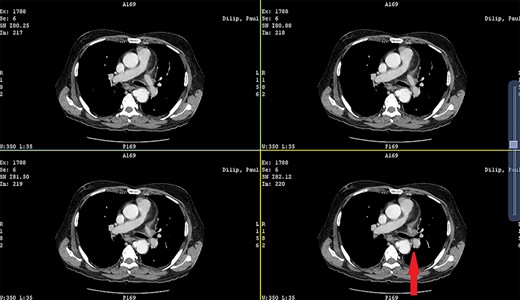

CECT showing the descending thoracic aortic aneurysm; the red arrow shows the communication of the aneurysm with the esophagus.

Patient 2: a 48-year-old hypertensive, non-diabetic gentleman, presented to the emergency with one episode of massive hematemesis. There was no history of dysphagia, jaundice, abdominal distension, pain abdomen or altered sensorium. Past history was significant for percutaneous coronary intervention with two drug-eluting stents performed 3 years ago, for which he was on aspirin. He had normal mentation, his BP was 90/60 mm Hg and his heart rate was 120/min. A general survey revealed pallor and rest of the systemic examination was normal. His Hb was 6.1 gram% and TLC was 6300 cells/mm3. Liver function tests, coagulation parameters, renal function and electrolytes were normal. Chest X-ray was unremarkable. He was initially resuscitated with intravenous fluid, packed red blood cells and a proton-pump inhibitor infusion. An urgent UGI endoscopy revealed a large depressed ulcer with a red spot located in the middle third of the esophagus. A diverticulum was seen in the lower end of the ulcer (Fig. 7). An endoscopic clip was applied to the margin for ease of identification. CECT thorax revealed a 6 cm saccular thoracic aortic aneurysm distal to the left subclavian artery, eroding into the esophagus (Fig. 8).

Surgery was emergently undertaken. A posterolateral thoracotomy was performed, and the aneurysmal segment of the aorta was seen originating 6 cm distal to the left subclavian artery. A partial bypass circuit was created, similar to the one described earlier. After cross-clamping the aorta both proximally and distally, the aneurysm sac was opened (Fig. 9). The aneurysmal segment of the aorta was replaced with a Dacron graft, taking care to preserve as many intercostal arteries as possible, while suture ligating the others (Fig. 10). The esophageal opening of the fistula was debrided and repaired with interrupted polypropylene sutures, superimposed with a vascularized intercostal muscle pedicle. The patient was successfully separated from the partial bypass, and a gastrostomy and jejunostomy were created. He was placed on broad-spectrum antibiotics postoperatively. He recovered well and had an uneventful post-operative course.